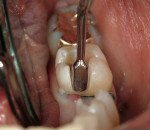

In vitro studies have demonstrated that the use of unidirectional glass-fiber reinforcement in the connector areas of FPDs contributes to significant composite reinforcement.29,36-38,66-68 Similar findings have been reported with a leno-weave UHMWPE and triaxial weave UHMWPE fiber.20,33,36 Fiber-reinforcing materials used by a dental laboratory are either resin pre-impregnated glass fibers, pre-polymerized composite resin surrounding glass fibers, biaxial braid UHMWPE, leno-weave UHMWPE, or a triaxial weave UHMWPE (Table 3). Typically, the preparation designs for the abutment teeth are inlay or onlay preparations (Figure 6A, Figure 6B, Figure 6C, Figure 6D). They are highly successful and can provide the patient with clinical service for more than 5 to 10 years.69 These restorations must be cemented using an adhesive resin technique with resin cements. Both etch-and-rinse adhesives with a self-cure or dual-cure composite resin cement or with a self-adhesive resin cement are indicated for cementing these restorations (Figure 7).36-38,70 Also, fiber-reinforcing materials are being used by dental laboratories in the fabrication of provisional restorations to reinforce and strengthen acrylic and composite-resin provisional materials.15,40,71